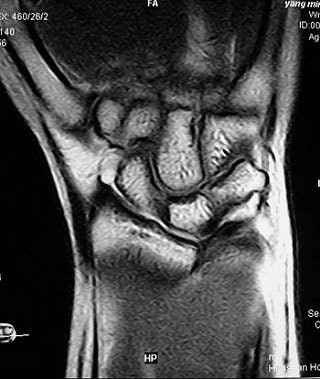

| The advantages of direct MR arthrography included clear visualization of synovial reaction and chondromalacia, and marrow edema, said Shuang and Xiaoyuan in their RSNA presentation. Images courtesy of Dr. Chen Shuang. |

On MR arthrography, the readers saw high signal intensity of contrast media at the ulnar insertion or radius attachment of the TFCC. Synovial reaction, chondormalacia and marrow edema were also clearly depicted on T2-weighted imaging and direct MR arthrography.

Shuang and co-author Dr. Fen Xiaoyuan suggested that when assessing for peripheral TFCC tears, imagers would find more diagnostic value from the high signal intensity at the radius attachment than at the ulnar insertion. They concluded that direct MR arthrography can reveal the peripheral attachment of the TFCC. Shuang told AuntMinnie.com that direct MR arthrography is now the preferred modality for TFCC imaging at his institution.